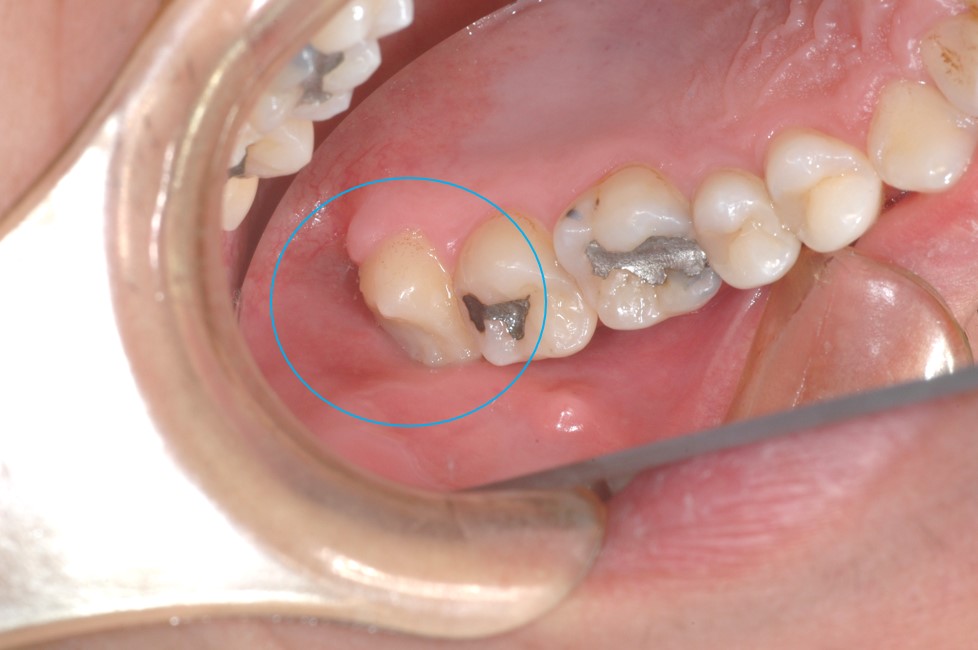

← 174.歯の移植手術(親知らず)